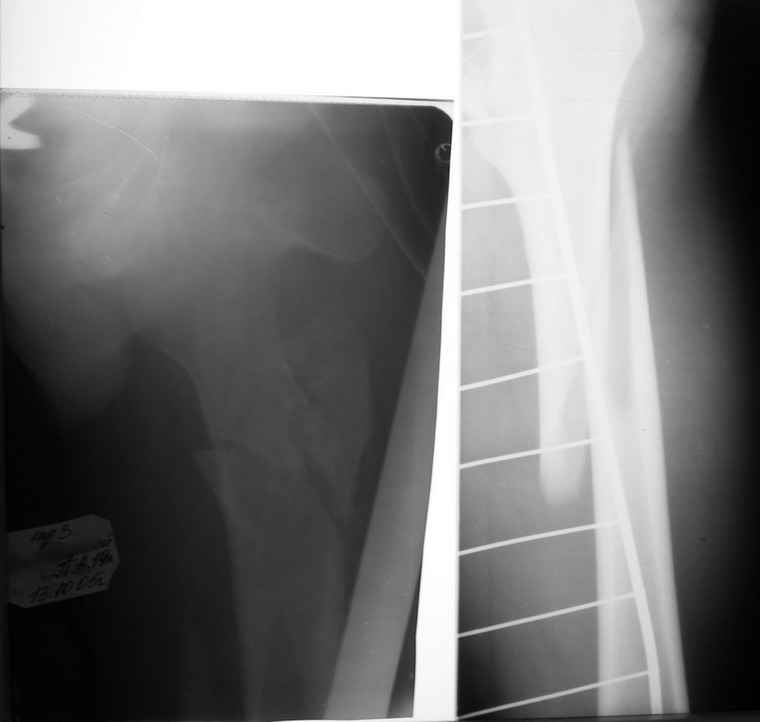

Вот снимки по свежей ситуации, парень 19 лет, длинный оскольчатый перелом бедра от шейки до в-с/3. давно уже ходит на своих ногах.

Делалось не мной (ассистировал), я на тазах "пока ещё не волшебник, а только учусь"